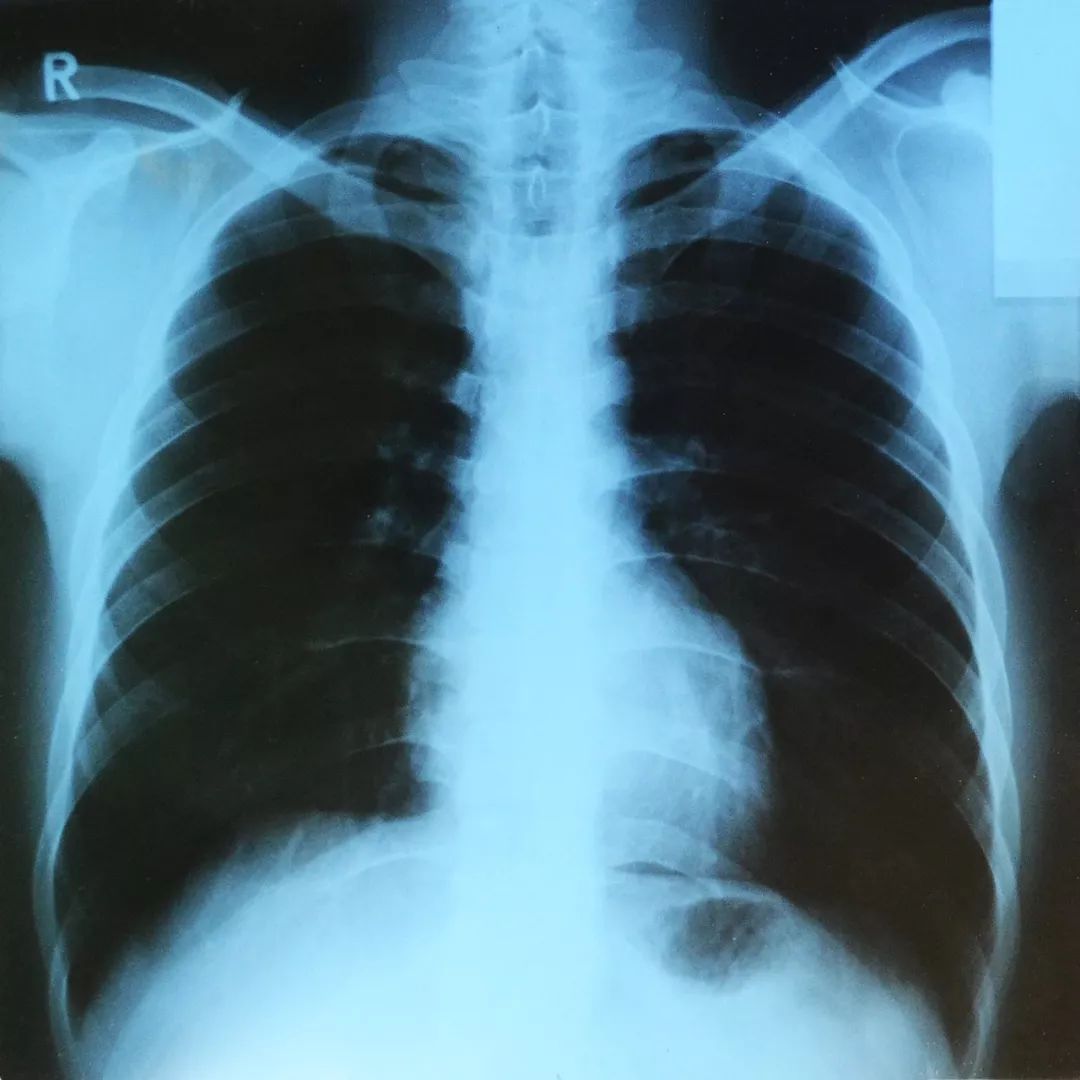

由于锁骨位于人体的最前方,所以拍X射线胸片时不会被其他骨骼或肌肉遮挡,可以清晰地看到它的轮廓。

因此,发现失踪者遗骨时,如果能够与其生前拍摄的X射线胸部照片进行对比,就能够通过锁骨鉴定身份。